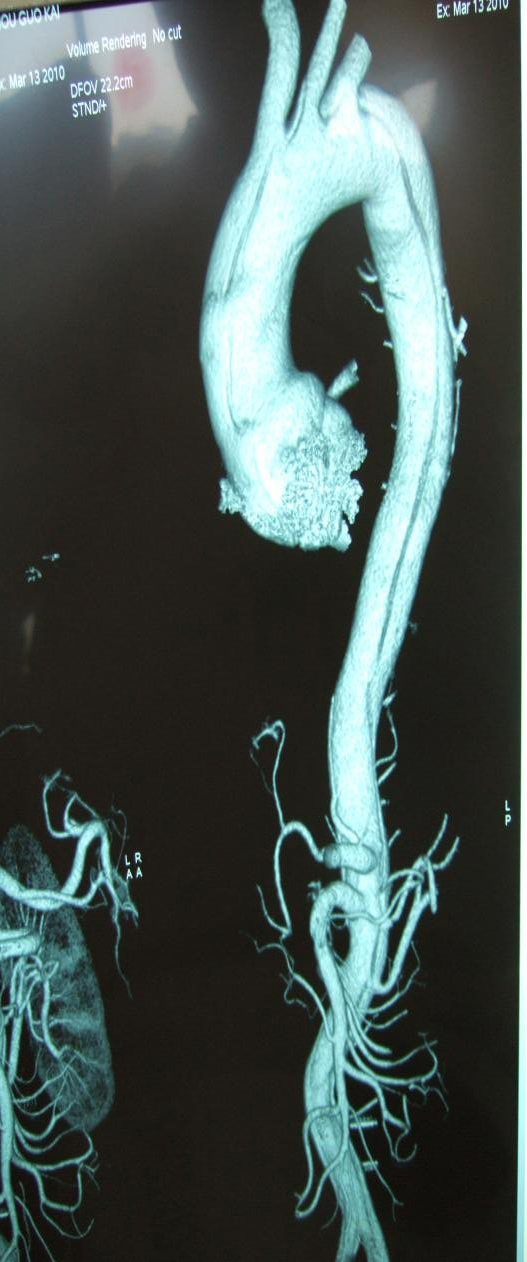

左图为A型主动脉夹层累及全主动脉;右图为B型夹层累及降主动脉以远